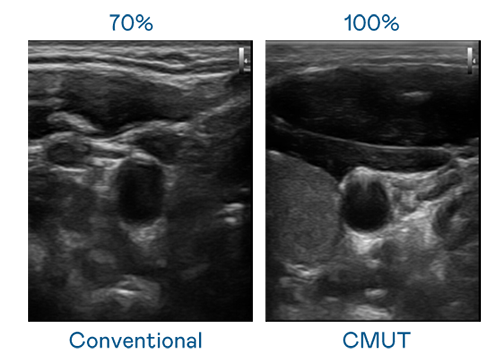

CMUT 技术是一种用电容式微机电元件来产生超音波讯号的技术。与传统 PZT 压电式技术相比,CMUT 频宽增加 30%,更宽频的超音波讯号让影像解析度大幅提升,是实现高影像品质医疗超音波扫描、促进精准医疗发展的关键技术。

大频宽带来超清晰影像

超音波影像的解析度高低,首先取决于探头能发出的讯号频宽。AGGAME CMUT 可提供高清晰的超音波讯号,提供高频宽、高灵敏度、影像纹理细节更高的超音波影像,协助医护人员缩短影像判读时间及利用精准的医疗影像进行诊断。